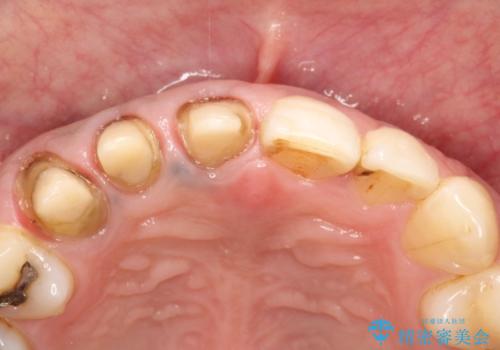

右上の前から1番目から3番目までの歯のかぶせ物を土台から再治療することとなりました。

金属の土台を、ファイバーコアという歯根にやさしく白いものに交換して、かぶせ物をオールセラミックにしました。